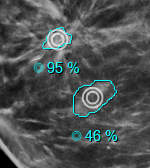

A DeepHealth CAD gyanúszintjeit a halmazvonalzóban található ikonban vannak feltüntetve. Egytől három sorig alacsony, közepes és magas gyanúszinteket jeleznek, ebben a sorrendben. Ha nincs vonal, az azt jelzi, hogy nincs gyanúszint meghatározva a CAD objektumban. Emellett ha a CAD objektum színt határoz meg a leletjelölőkre, a szín alkalmazásra kerül a képen és a halmazvonalzó grafikán. Ezt a funkciót az Opciók/Prezentációs állapotok/Mammográfiás CAD SR beállítási oldalon található Szín használata CAD jelölőkhöz beállításnál lehet letiltani.

A nézegető támogatja a ScreenPoint Transpara CAD objektumokat.

A Transpara logóval ellátott CAD fejléc tartalmazza a meszesedés és a tömegtalálatok számát, az algoritmus verzióját és a Transpara pontszámot (0 és 10 közötti egész érték).

A meszesedéseket gyémánt körvonal és az egyes meszesedések kontúrja jelöli.

A tömegeket a kontúrjuk jelöli (plusz az alapértelmezett marker, ha engedélyezve van).

A Screenpoint-hoz tartozik egy további lelettípus, a "döntéstámogatás", amely egy általánosabb vizsgálati területet ír le. Egyelőre a Transpara az egyetlen CAD, amely ezt a típust használja, de ez a jövőben változhat. Ahhoz, hogy az eszköz általánosabb legyen, a nézőke ezt a lelettípust "vizsgált területnek" (ROI) nevezi.

Mind a globális, mind a helyi CAD menübe új beállítási lehetőség került be az vizsgált területek megjelenítésére/elrejtésére. Az alapértelmezett a kikapcsolt állapot.

A Transpara esetében a vizsgált területek színkódolt körökként jelennek meg, amelyekhez általában - de nem mindig - pontszám is tartozik.

Lásd: ScreenPoint Transpara

A DeepHealth Saige-Q SR objektumok támogatásával bővült. A triázs fejlécében megjelenik az algoritmus neve és verziója, valamint az esetértékelés típusa és értéke.